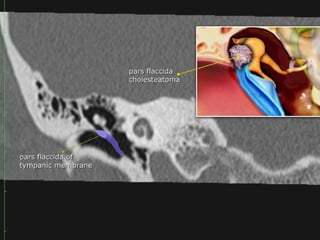

Tympanic membrane

 The tympanic membrane or eardrum is a cone-shaped membrane

that separates the external ear from the middle ear.

 The pars flaccida is the upper fragile part that is associated with

eustachian tube dysfunction and cholesteatoma.

 The pars tensa is larger and more rubust and associated with

perforations.

The handle or manubrium of the malleus is connected to the central

part of the tympanic membrane, which is called the umbo.